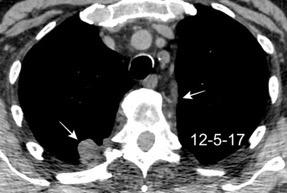

Signos radiológicos TC

Hallifax RJ et al. State-of-the-art: Radiological investigation of pleural disease Respiratory Medicine 2017

Nivel hidroaéreo o burbujas

Forma lenticular o elíptica Ángulos obtusos

> Grasa Extrapleural (60-80%)

Situación no gravitacional (no siempre)

Compresión de estructuras pulmonares

Límite muy bien definido Tabicación

Patrón ecográfico de empiema

Empiema

El derrame paraneumónico se convierte en complicado en 5-10% de los casos

Engrosamiento de la pleura parietal 36/ 59 exudados (61%) 56% de D. paraneumónicos 100% de empiemas Especificidad.. 96%.

Exudado versus trasudado.

Aquino SL, et al. Pleural exudates and transudates: diagnosis with contrast-enhanced CT. Radiology 1994

Signo de la Pleura separada “Split pleural sign”

Capas pleurales de grosor uniforme realzadas por el contraste

Dr. César Pedrosa

No específico de empiema. Indica “exudado”. 68% de pacientes con empiema pleural.

Capas pleurales de grosor uniforme

Realce grasa extrapleural (30%)

> Grasa Extrapleural. (60-80%)

Kraus GJ. Split pleural sign. Radiology 2007